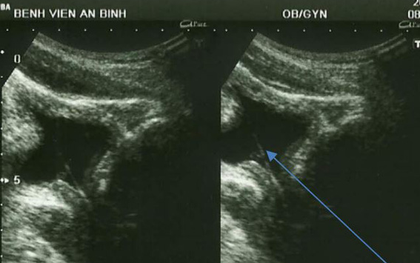

Tự khều sỏi thận, người đàn ông bị vướng cỏ trong… “chỗ hiểm”

Nghi ngờ mình có sỏi thận trong niệu, người đàn ông tự lấy cọng cỏ chọc vào “lỗ sáo” ở bộ phận sinh dục để khều ra. Hậu quả là cọng cỏ bị đẩy vào sâu bên trong khiến anh đi tiểu ra máu liên tục.